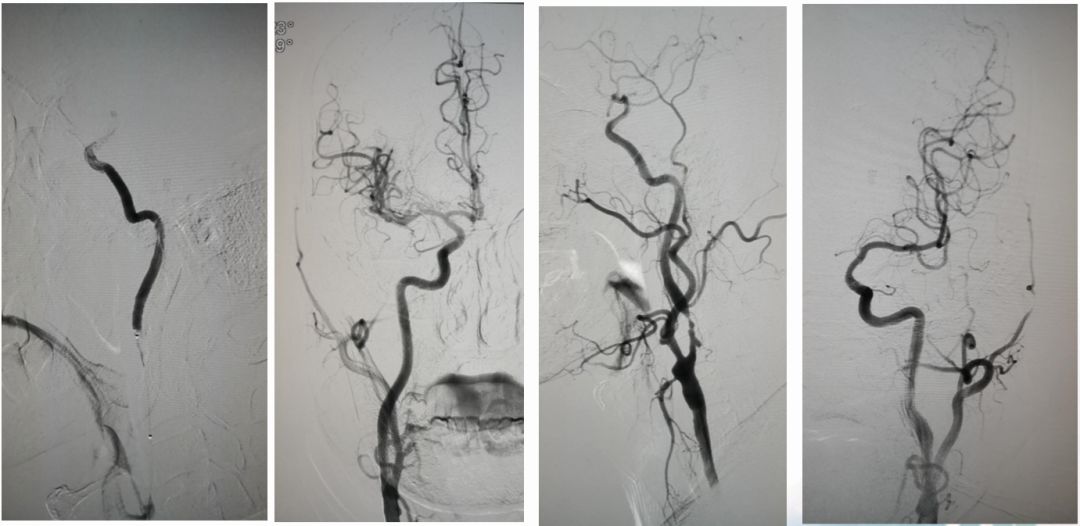

术前造影:

串联病变

ASITN/SIR 2级

球囊扩张

微导管在血栓远端造影

支架到位释放透视图+造影图

异常早显静脉

取出栓子

术后正侧位造影图片